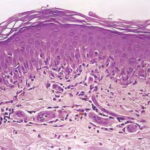

Histopathology. EM is considered the prototype of the vacuolar form of interface dermatitis . The early changes include vacuolization of the basal cell layer; tagging of lymphocytes along the dermal-epidermal junction; and a sparse, superficial, perivascular lymphoid infiltrate . Necrosis of individual keratinocytes in the basal unit occurs, which is the hallmark of EM. Because of its acute nature, there is an orthokeratotic stratum corneum. Mild spongiosis, papillary dermal edema, and extravasation of red blood cells are seen. As the lesion becomes more developed, there is a moderate lichenoid infiltrate of Iymphohistiocytes at the dermal-epidermal junction with exocytosis. More apoptotic keratinocytes within and above the basal epidermal layer are present. The |

intensity of epidermal necrosis varies from vacuolated individual keratinocytes surrounded by lymphocytes (satellite cell necrosis) at the basal unit to confluent necrosis in association with intraepidermal and subepidermal vesicles. The dermal infiltrate comprises lymphocytes and histiocytes. Eosinophils may also be present. Although one study has noted a significant number of eosinophils in drug-induced EM, this has not been noted by others. In the authors’ estimation, a generous number of eosinophils exclude EM. One study has found that an acrosyringium concentration of apoptotic keratinocytes in EM is a clue to a drug etiology . In early lesions of SJSITEN, apoptotic keratinocytes are observed scattered in the basal layer of the epidermis. In established lesions, there are numerous necrotic keratinocytes, even full-thickness epidermal necrosis, and a subepidermal bulla. The dermal inflammatory infiltrate is sparser in TEN than in EM (Fig. 9-278). Extravasated erythrocytes are commonly found within the blister cavity. Melanophages within the papillary dermis occur in late lesions. Eccrine epithelium shows a variety of changes from basal cell apoptosis to necrosis of the duct. |

In general, EM shows less epidermal necrosis, more dermal inflammation, and exocytosis, whereas SJS and TEN reveal more epidermal necrosis, less dermal inflammation, and exocytosis. However, due to the overlapping histologic features among EM, SJS, and TEN, histologic examination-while important for recognizing the spectrum of disorders-is not reliable for classifying the disease. Correlation with clinical presentation is essential. |